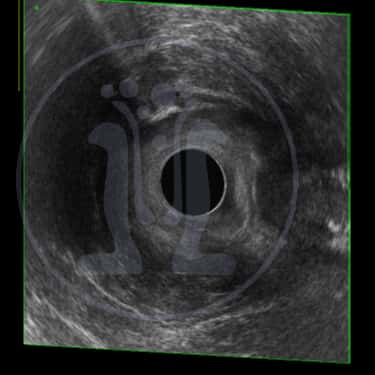

Ασθενής 44 ετών που εξετάσαμε δεύτερη φορά μετά από 14 μήνες έμεινε αθεράπευτος γιατί κανείς δεν ήθελε να τον αναλάβει. Είχε δύο ράμματα seton σε λάθος θέση ενώ στην σωστή θέση δεν υπήρχε ράμμα seton. Πολλαπλές επεμβάσεις είναι απαραίτητες για την τελική θεραπεία του προβλήματος του.